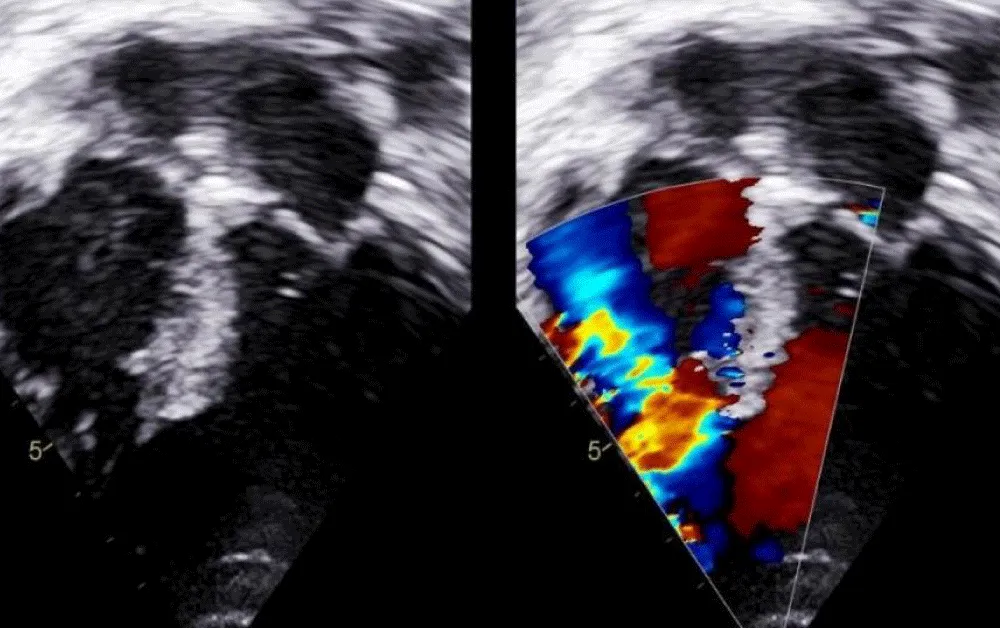

There was no use of transesophageal echocardiography due to the unavailability of a suitable probe. Left Ventricular angiogram was done to determine the exact location of the VSR (Figure 2). Cannulation of the right femoral artery and right internal jugular vein or right femoral vein was performed using the Seldinger technique. A guidewire (03500 Terumo guidewire) was introduced from the femoral artery, through the aorta into the left ventricle, and advanced through the VSR into the right ventricle and pulmonary artery. A second snaring wire was introduced through the vein (Either jugular or femoral) to connect to the guidewire in the pulmonary artery. By retracting the snared wires, the guidewire now forms an arteriovenous (AV) loop. The delivery sheath was advanced from the venous side loop over the guidewire through the VSR into the left ventricle. Correct positioning of the delivery sheath is confirmed in fluoroscopy/TTE. The guidewire is then retracted leaving the delivery sheath in position. After the echocardiographic confirmation occluder device was deployed across VSR using the delivery sheath (Figure 3). Correct positioning of the device and closure was confirmed by transthoracic echocardiography and/or fluoroscopy. If placement is satisfactory, the occluder is released. Post-procedure Left ventricular angiography and transthoracic echocardiography (Figure 4) were done to confirm the position and to rule out the presence of any residual shunt. We did not perform transoesophageal echocardiography for delineation of post-MI VSR, in any of the patients of our series due to the lack of availability of probes. In two cases we did not use any contrast agent (angiography) to delineate VSR because both patients had very high levels of urea and creatinine. Out of 11, in 10 cases, we made use of the femoral-jugular mode of access and created an AV loop. In one case we made a femoral arterio-venous loop. The veno-venous loop though described in literature was not used in this study.

Figure 3: After echocardiographic confirmation occluder device deployed across VSR using the delivery sheath.